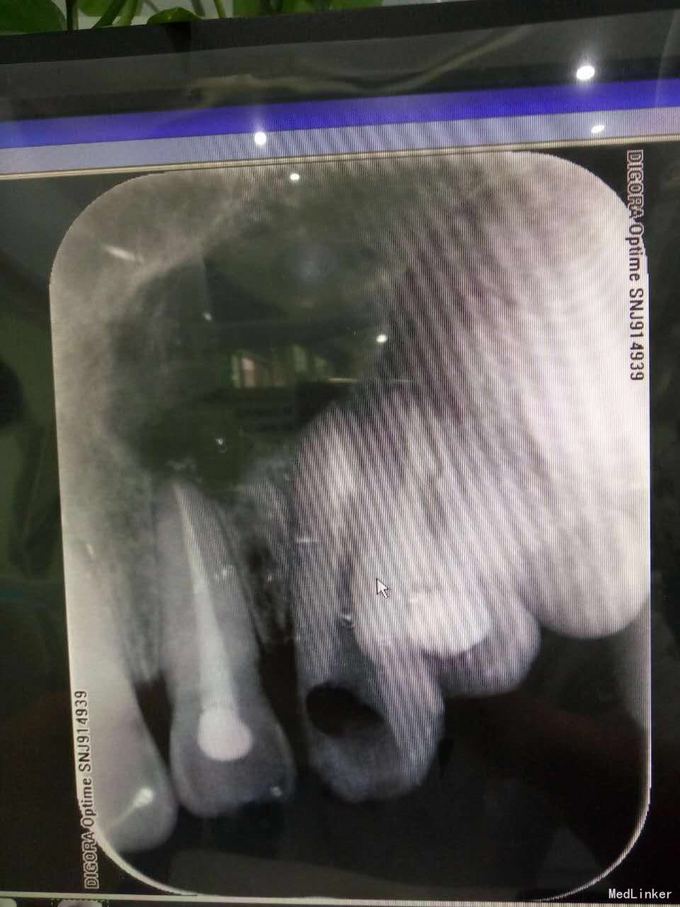

24牙合面龋坏,龋坏较深,未穿髓,龈红,无窦道,无松动 23牙牙体完整无明显松动 22牙牙体完整,腭侧有窦道,无明显松动 X线示23牙根尖牙周组织可见1cmX10cm囊肿,波及22牙及24牙

22牙牙髓部分坏死 23根尖囊肿 24牙髓坏死 1.22牙23牙24牙RCT 2.转外科行23牙囊肿摘除术 23牙MTA根尖封闭,拍片,确定根尖封闭良好,使用热牙胶垂直加压充填,流动树脂垫底,Z350树脂充填抛光 22牙24牙根充,流动树脂垫底,Z350充填抛光